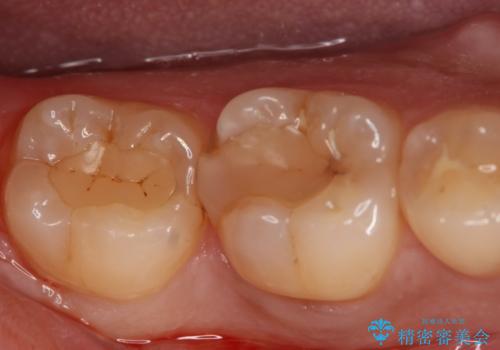

- 右下6・7番の治療のやり変えを主訴に来院された患者様です。

保険の材料が劣化し中で虫歯が進行しているため、古い材料と虫歯を全て除去した上で詰め直す必要がありました。

切削量・形態を考慮し、セラミックインレーでの治療を計画しました。